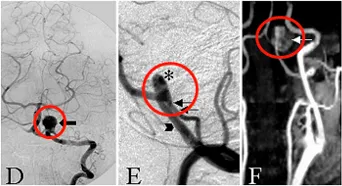

图1G:CT显示动脉瘤的血栓形成及部分钙化。

术后情况:病人在手术当天即神志清楚,没有出现新发的神经功能缺损。在术后第一天的检查中,未发现局部或远端梗死和吻合口再出血(图2A-B)。MR显示脑干压迫效应解除(图2C-和D),术后血管造影显示吻合的PICA充盈良好、血流通畅(图2E-F)。术后恢复顺利,无术后并发症。经过7年的随访,声带麻痹已痊愈,生活正常。

图2A-B:CT显示动脉瘤囊切除和VA-PICA吻合术后,远外侧入路的骨磨除部分。

图2C-D:术后MR显示动脉瘤体切除。

图2E-F:术后血管造影显示成功的VA-PICA吻合术,不同直径的VA(星号)和PICA(双箭头)以及远端VA上的永久夹闭(单箭头)。